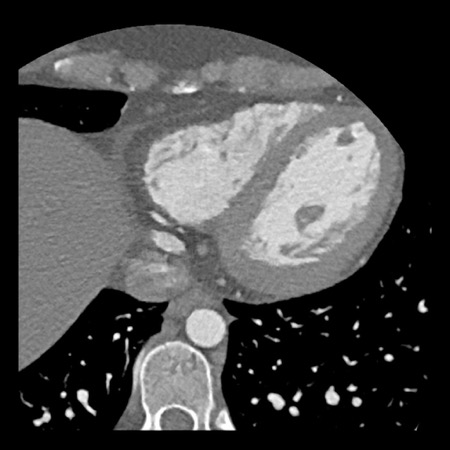

case 1 – CAD-RADS 2/P1

First, scroll through the scan.

Not all images are included. Some images without any abnormalities are skipped

from the series.

How would you describe the findings on the coronary CTA?

The findings are:

- Agatston score of

this patient was 14 (P1). Please, also note the calcification of the aortic valve. - Some partially

calcified and calcified plaques are present in the LAD with mild stenosis

(25-49%). - Calcified-plaque in

the LCX causing minimal stenosis (<25%). - Non-calcified

plaque in the distal RCA causing minimal stenosis (<25%). - This patient classifies

as CAD-RADS 2/P1, which means no further workup is needed.